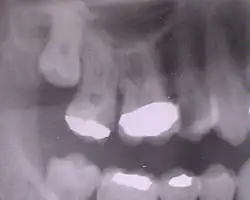

Zubní plomby pod rentgenem

Zubní plomba (zubní výplň) zabraňuje šíření kazu, tím že zakrývá kazem otevřenou zubní tkáň. Zubní plomba tedy nahrazuje ztracené části zubní korunky, čímž je zub znovu schopen vykonávati svoji funkci. Takovéto zubní výplně se vyrábí z různých materiálů[1], jako např. z Newtonova kovu.

Nejstarším dnes ještě používaným typem plomby je zubní amalgám (směs stříbra a rtuti), který je některými zdroji označován jako určité zdravotní riziko.[2] Amalgám se v zubním lékařství používá více než 150 let, některé ordinace se však dnes jeho užívání brání a pacienty chrání při odvrtávání starých plomb odvětráváním a použitím gumové blány.[3] Moderní plomby jsou po fyzikálních a chemických vlastnostech velice podobné, někdy i do značné míry shodné se zubními tkáněmi. Reakce na podněty (např. teplo, chlad) je daleko lepší, protože je podobná nebo totožná jako u přirozené zubní tkáně. Ideální plomba se roztahuje nebo zmenšuje stejně jako přirozený zub.